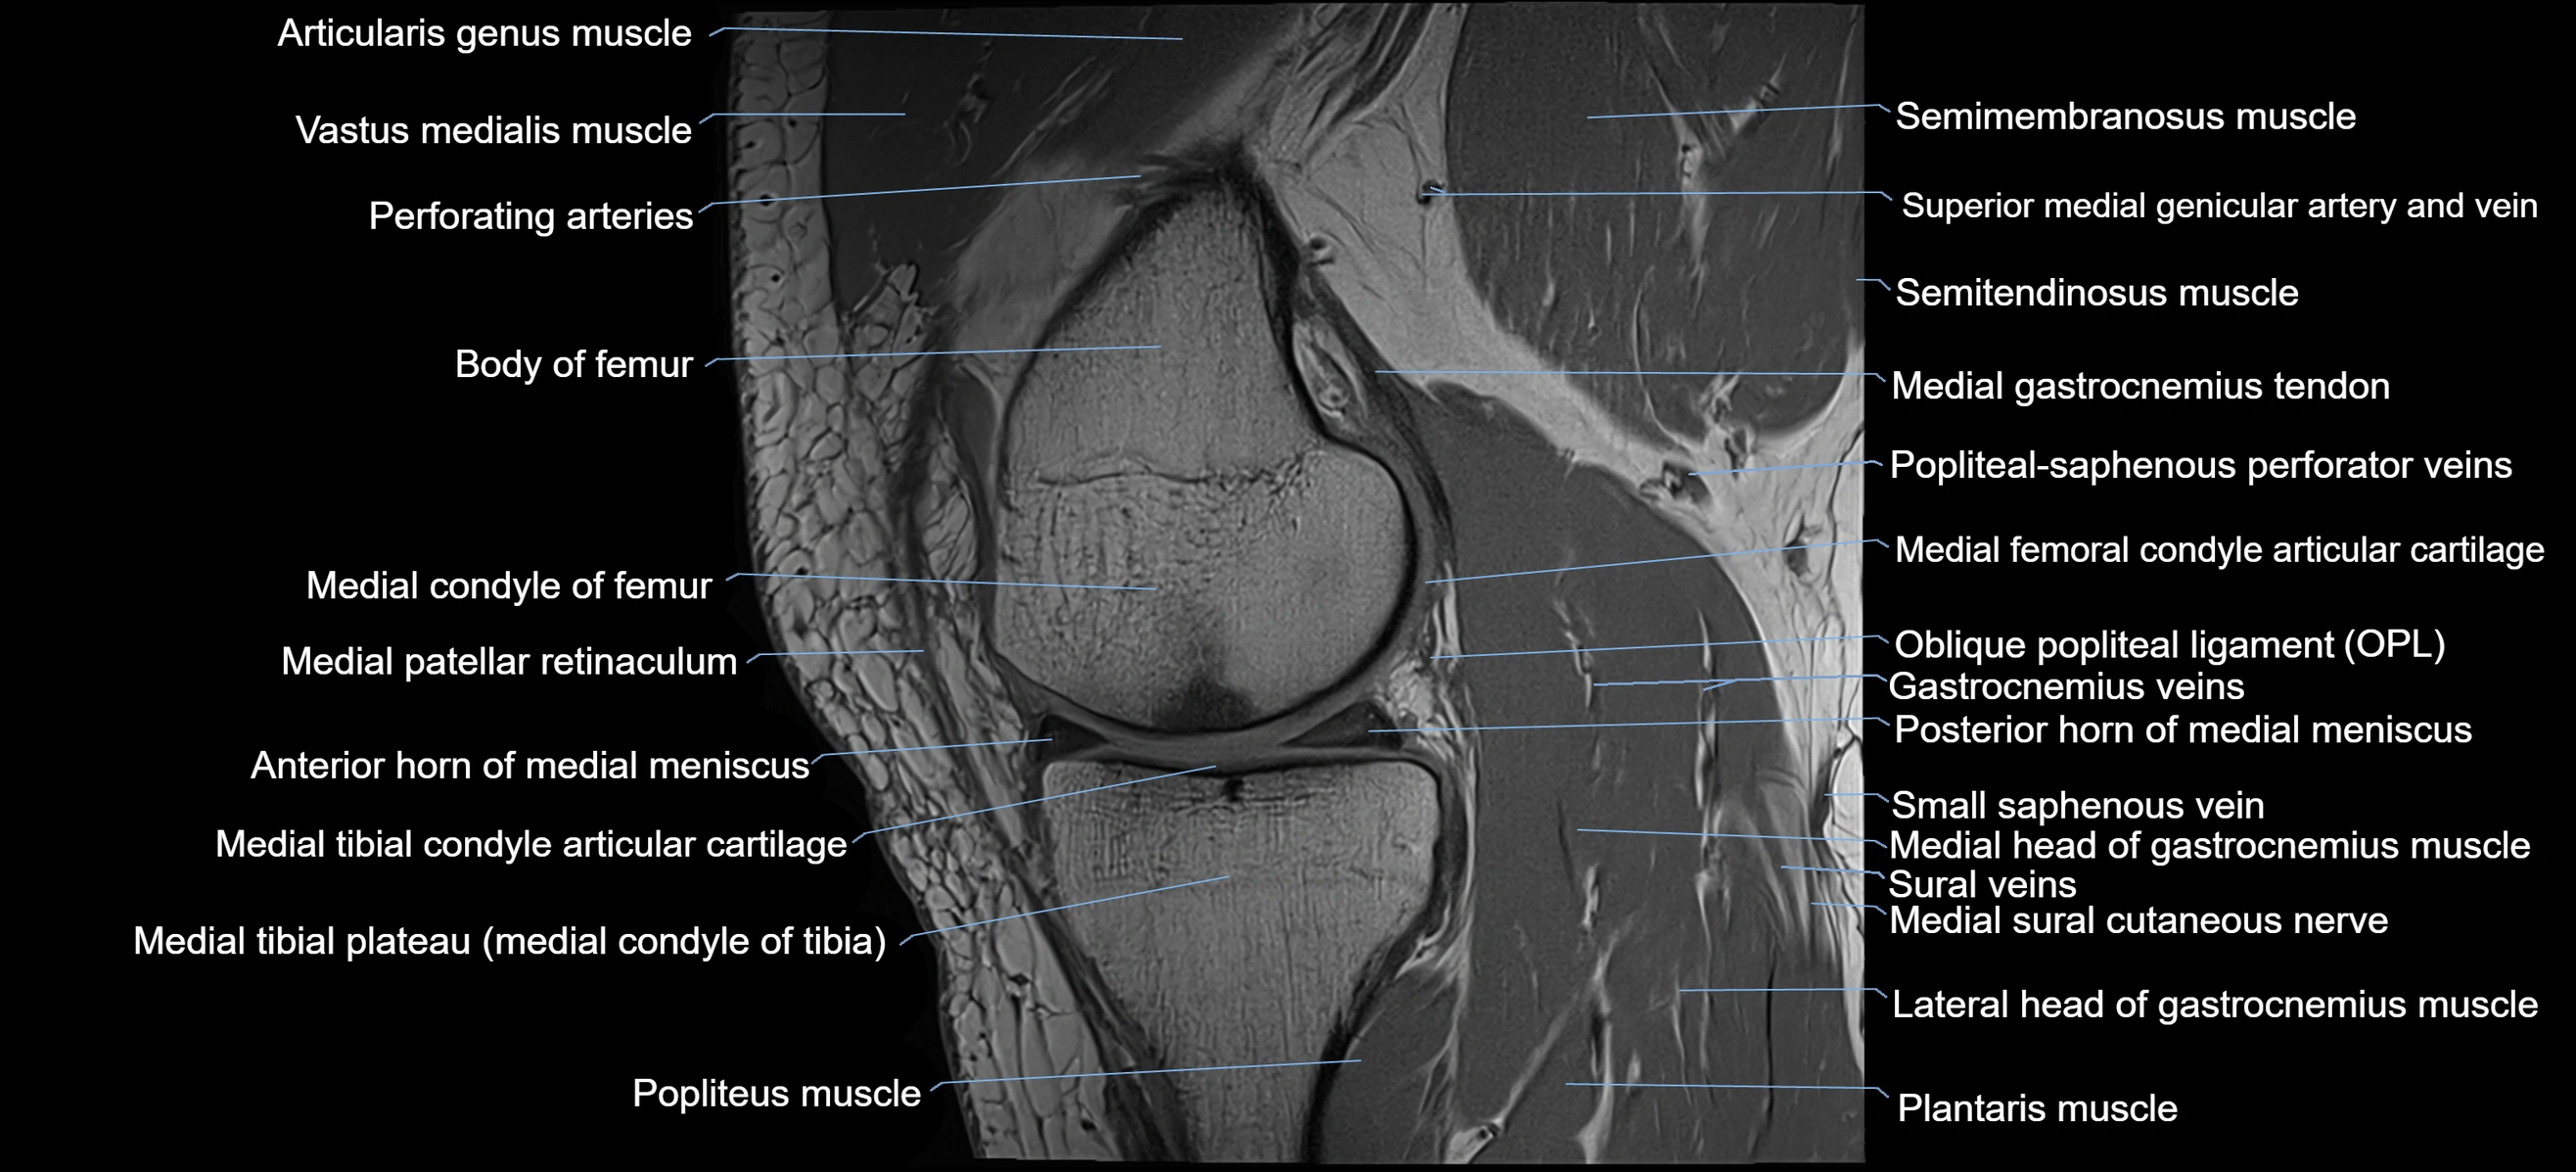

- Anterior horn of medial meniscus

- Body of medial meniscus

- Medial condyle of femur

- Medial condyle of tibia

- Medial gastrocnemius tendon

- Medial head of gastrocnemius muscle

- Medial meniscus

- Medial patellar retinaculum

- Medial sural cutaneous nerve

- Medial tibial plateau

- Oblique popliteal ligament

- Perforating Arteries (Knee joint)

- Plantaris muscle

- Popliteal artery

- Popliteal vein

- Popliteal–Saphenous perforating veins

- Popliteus muscle

- Posterior horn of medial meniscus

- Sartorius muscle

- Semimembranosus muscle

- Semitendinosus muscle

- Small saphenous vein

- Soleus muscle

- Superior medial genicular artery

- Superior medial genicular vein